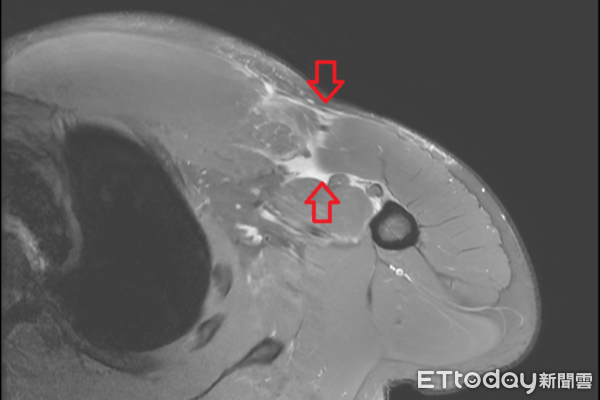

▲一名男性健身意外發生「右側胸大肌斷裂」。(圖/院方提供)

27歲的林先生有規律的健身習慣,某次臥推訓練後,在放槓鈴的瞬間,突然感到右側胸口劇烈疼痛,右上肢越發無力,伴隨瘀青腫脹,就醫檢查才發現是「右側胸大肌斷裂」,隨即安排胸大肌肌腱縫合手術。醫師提醒,胸大肌斷裂屬於相對罕見的運動傷害,臨床症狀包括急性劇痛、局部腫脹與瘀青、患側力量明顯下降等。